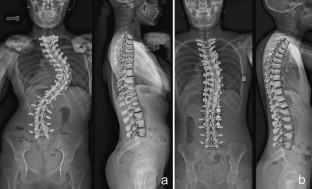

Adolescent idiopathic scoliosis treated with posteromedial translation: radiologic evaluation with a 3D low-dose system

Computed tomography can be used for three-dimensional (3D) evaluation of adolescent idiopathic scoliosis (AIS) patients, but at the expense of high radiation exposure, and with the limitation of being performed in the supine position. These drawbacks can now be avoided with low-dose stereoradiography, even in routine clinical use. The purpose of this study was to determine the 3D postoperative correction of AIS patients treated by posteromedial translation.

Forty-nine consecutive patients operated for AIS (Lenke 1–4) using posteromedial translation were included. Corrections were evaluated preoperatively, postoperatively and after at least 2 years using the EOS imaging system. 3D angles were measured in the plane of maximum deformity.

Mean number of levels fused and operative time were 13.5 ± 1 and 215 ± 25 min, respectively. Main thoracic, proximal thoracic, and lumbar curves corrections averaged 64.4 ± 18, 31 ± 10 and 69 ± 20 %, respectively. Mean T4–T12 kyphosis increased 18.8° ± 9° in the subgroup of hypokyphotic patients. Mean apical vertebral rotation reduction was 48.3 ± 20 %. Trunk height gain averaged 27.8 ± 14 mm. There was no pseudarthrosis or significant loss of correction in any plane during follow-up. Two patients (4 %) developed asymptomatic proximal junctional kyphosis, despite having normal thoracic kyphosis. Their sagittal balance was shifted posteriorly by 36 and 47 mm, respectively, by the operation, but revision surgery was not performed.

Low-dose stereoradiography provided 3D reconstructions of the fused and unfused spine in routine clinical use. Postoperative 3D analysis showed that posteromedial translation enhanced sagittal balance correction, without sacrificing frontal or axial correction of the deformity.

Fig. 2